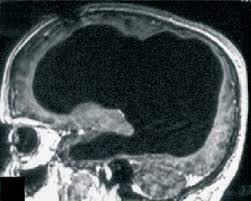

Iniţial, bărbatul a vizitat medicul pentru că simţea o slăbiciune în piciorul stâng, însă ecografia craniană a dezvăluit o problemă mai gravă. O mare parte din creierul său era umplută de lichid, având doar un strat subţire de ţesut al creierului, părţile interne fiind erodate aproape complet.

Cercetătorii consideră că o mare parte din creierul bărbatului a fost distrus treptat, de-a lungul a 30 de ani, condiţie cunoscută sub denumirea de hidrocefalie. Bărbatul fusese diagnosticat cu această afecţiune când era copil şi a fost tratat cu un stent, însă la vârsta de 14 ani acesta a fost îndepărtat. De atunci, cea mai mare parte a creierului său a fost erodat.

Deşi i-a rămas o mică bucată din creier, bărbatul nu avea dizabilităţi mentale, IQ-ul său fiind de 75 de procente. Acesta lucra ca funţionar public, era căsătorit şi avea doi copii, starea lui de sănătate fiind relativ bună.